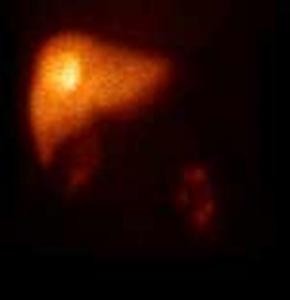

Many tumors express somatostatin receptors, especially the various types of neuroendocrine tumors (for example carcinoid, meningeoma, medulloblastoma and neuroblastoma). These can be investigated with somatostatin analogue peptides, most commonly with pentetreotide, an 111In isotope labeled peptide (OctreoScan). This examination is primarily significant in carcinoid and GEP (gastroenteropancreatic) tumor (gastrinoma, insulinoma, glucagonoma, VIPoma) diagnostics. Although GEP tumors present with a severe clinical picture, they are usually small and their detection with other imaging modalities is difficult. For this reason, somatostatin receptor scintigraphy is the recommended method of first choice. If the carcinoid is well differentiated, it is able to detect the lesion and possible metastases. Furthermore, it is useful in therapy monitoring and in cases of planned liver transplantation to rule out extrahepatic metastases. (Figure 13.)

Image

a

b

c

13. Somatostatin receptor scintigraphy (Octreoscan). Planar anterior (a), transversal (b) and coronal (c) fusion SPECT-CT images. Multiplex liver metastases, the primary neuroendocrine tumor is in the head of the pancreas.